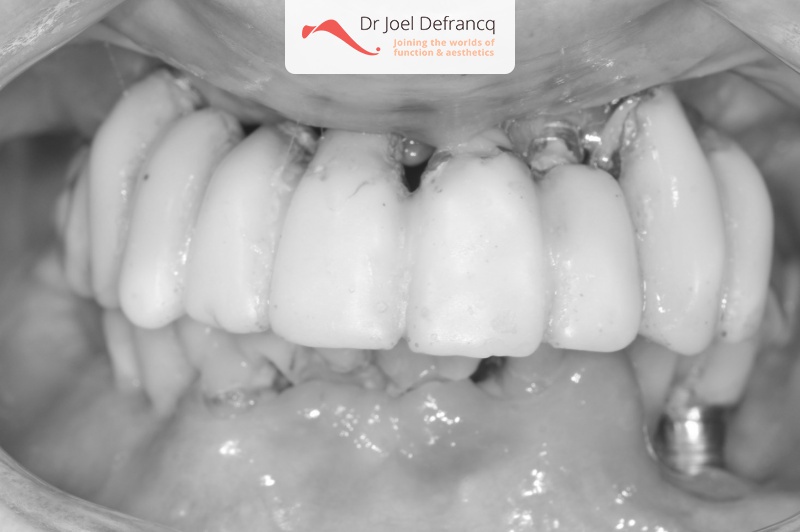

Kait: new teeth in a week - 4 zygoma implants

Behandeling tandheelkundige implantaten

- Vaste tanden op implantaten (bovenkaak)

- Vaste tanden op implantaten (onderkaak)

- Zygoma implantaten